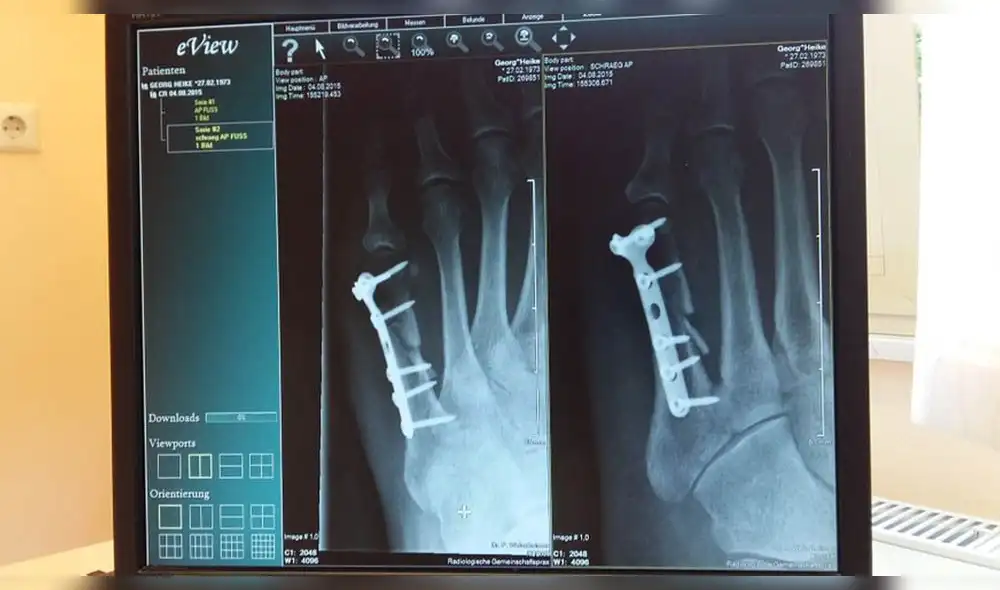

Rusia: desarrollan un método para acelerar la soldadura de huesos